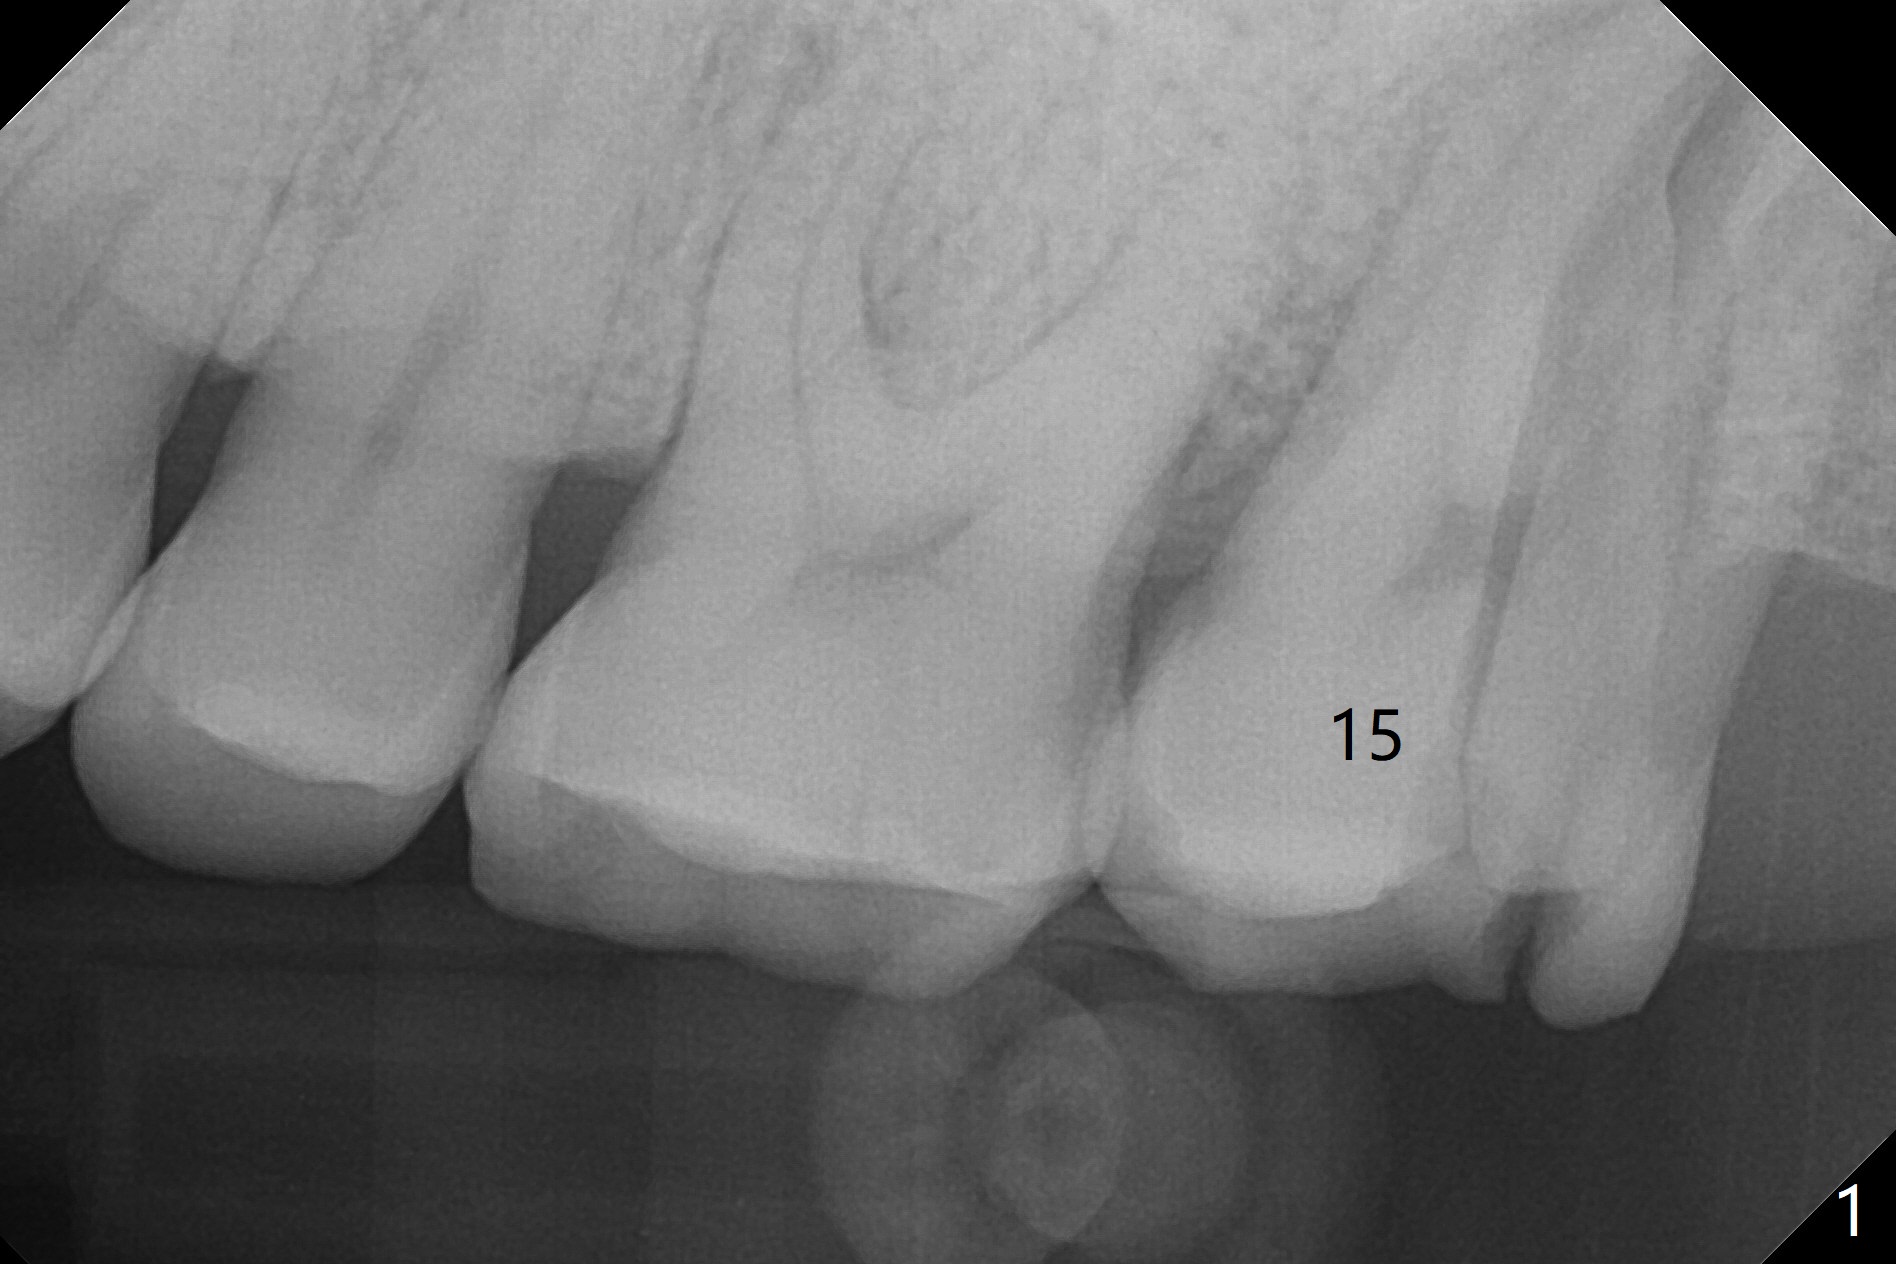

Large Upper 2nd Molar Socket After Vertical Root Split

A 45-year-old man with #4 crown fracture and C deciduous tooth returns to clinic with chief complaint of "chewing pain" UL. It seems that the distal marginal ridge of the tooth #15 has simple oblique subgingival fracture. With one carpule of Xylocaine, the distal portion cannot be removed because of pain. X-ray reveals vertical root fracture (Fig.1,2). With additional carpules of Septocaine and Marcaine, the tooth is removed. The socket is large with abundant granulation tissue. After debridement, a large amount of Vanilla graft and a whole piece of Osteogen plug is placed for socket preservation (Fig.3).